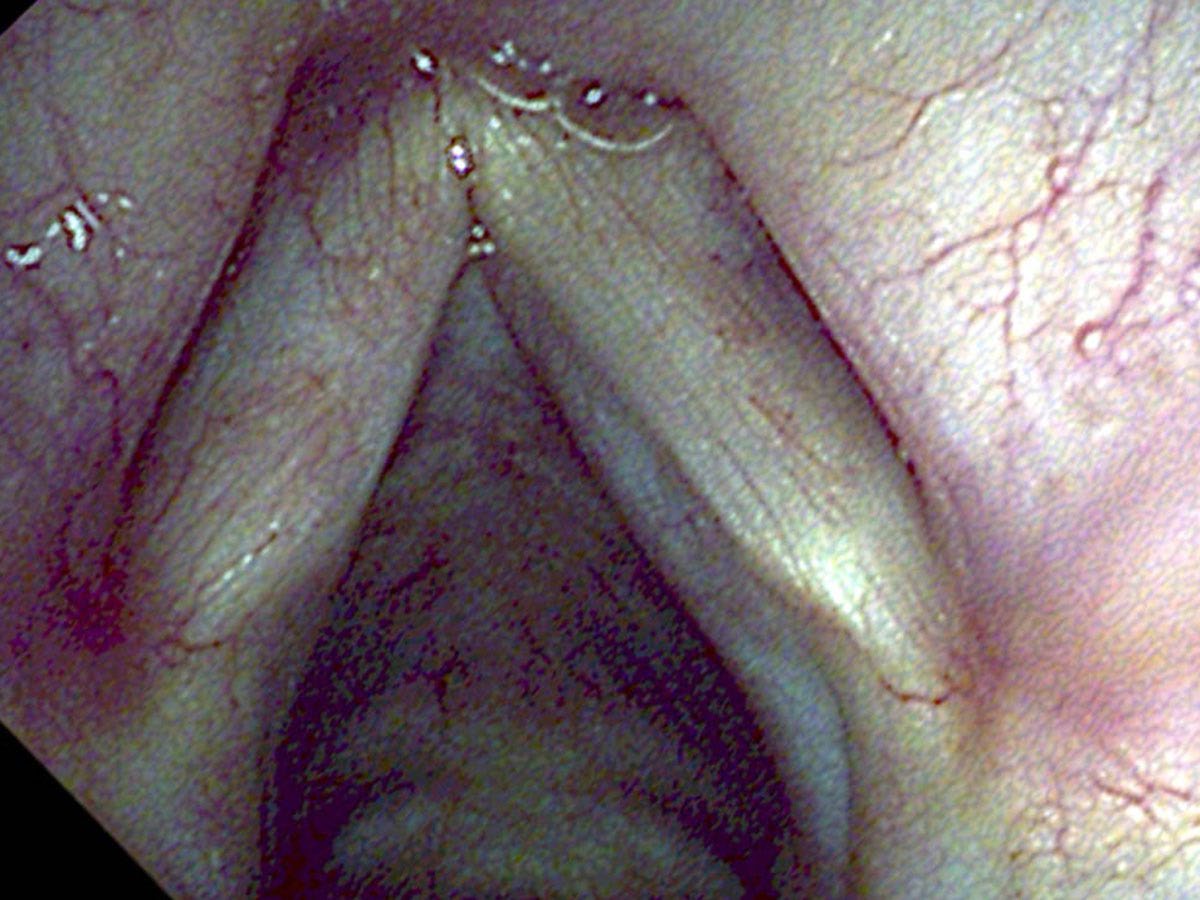

Treatment with the KTP laser effectively destroyed the blood supply to this area and burned off the white spots so there was no specimen for a pathologist to look at. I really cannot say this time whether the leukoplakia was benign or cancerous except that it grew rather slowly for three years. After treatment of both the leukoplakia and the feeding blood vessels, the white spots have not returned, although we continue with regular examinations of her vocal cords. We could treat the leukoplakia again if it comes back.

Careful close observation, with carefully directed precise treatment when necessary, may be a successful substitute for what, in the past, was essentially overtreatment.

Leukoplakia may be benign or at times it may represent a cancer. After identifying abnormal white spots on the vocal cord, options for patients include treatment that removes the white patches or makes them go away, or careful observation and removing any white patches that grow over time. Cutting away part of the normal vocal cord along with leukoplakia, because it might be a cancer, might have the same cure rate, but sacrifices voice quality when a significant amount of normal tissue is removed.

- The KTP laser can treat leukoplakia and its feeding blood vessels in the office, without removing tissue for pathology — useful when a lesion appears stable over time.